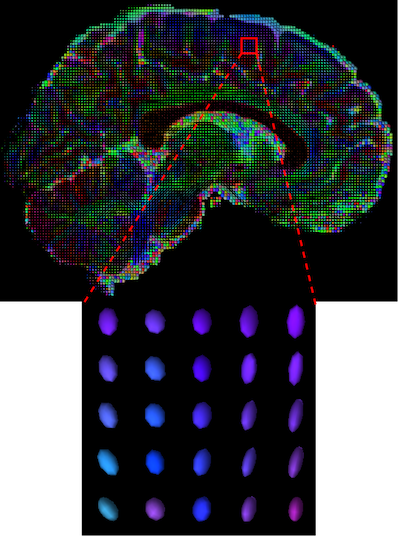

Diffusion Weighted Imaging (DWI) is a non-invasive magnetic resonance imaging (MRI) modality developed to monitor water diffusivity and reveal the micro-structure of the human body [1]. While conventional structural MRI sequences (e.g. T1, T2) provide information about the general morphological information of the brain, DWI provides additional information regarding brain dynamics with water diffusivity as a proxy. This set of sequences acquired with different gradient directions can then be summarised using a Diffusion Tensor Imaging (DTI) model to uncover microstructural information. Based on the fact that different tissues have different diffusion properties, the DTI model explains the directionality of the water diffusivity and its corresponding quantitative anisotropy [2]. The diffusion of a particular voxel can be characterized as an ellipsoid (Figure 1(a)) that can be mathematically formulated as a symmetric tensor matrix (Figure 1(b)). The coordinate system is typically aligned with the main magnetic field and body of the patient. Since the relationship between two principal directions is theoretically symmetric, i.e., , and , only 6 unique coefficients are needed to construct the tensor at a particular voxel.

The visualization of inpainted results (showing the whole diffusion tensor for each voxel) generated from different models are demonstrated in Figure 3, where the tensor is represented in RGB coding that colours red, green and blue represent diffusion in the x, y, and z axes respectively. One typical example of reconstruction in the disrupted ROIs has been zoomed for visualization. Compared to the ground truth, TW-BAG is able to generate more distinct orientations following the original distribution and intensity across sagittal, coronal and axial views, which could demonstrate water diffusivity (denoted by eigenvalues of tensor model) more accurately. As indicated in Figure 4, the boundaries and textures of the FA map for TW-BAG are less blurry than the other competing models, validating the effectiveness of TW-BAG from a neuroscience perspective.